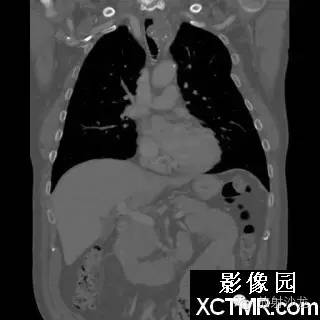

On the contrast-enhanced CT of the chest, there is a heterogeneous mass arising from the left lateral wall of the trachea. The mass demonstrates extratracheal extension as well as extension into the tracheal lumen. (Figure 1 and Figure 2). The mass also contains internal calcifications (arrows), representing chondroid matrix mineralization (Figure 3 and Figure 4).

胸部增强扫描示气管左侧壁发出一不均质的肿块影,肿块向气管内外扩展(图1、2)。其内可见钙化影(箭头),代表软骨基质的钙化(图3、4)。